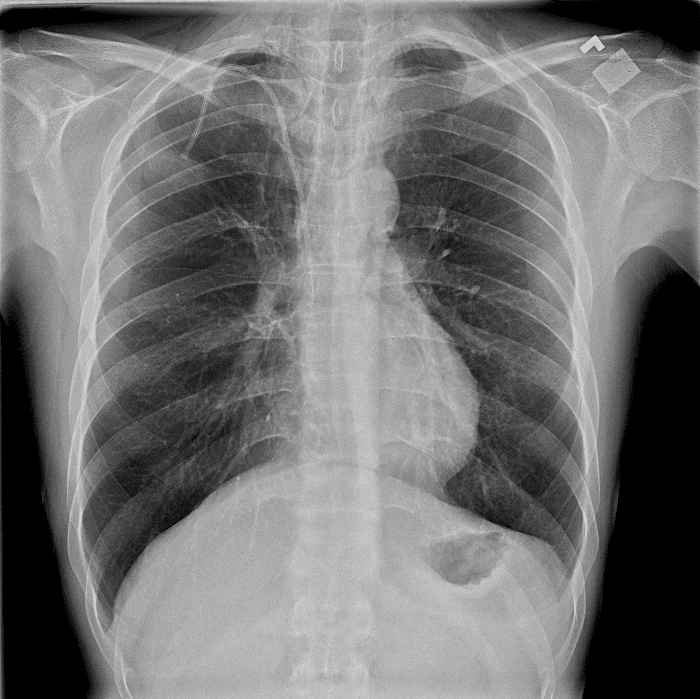

Practice Cases